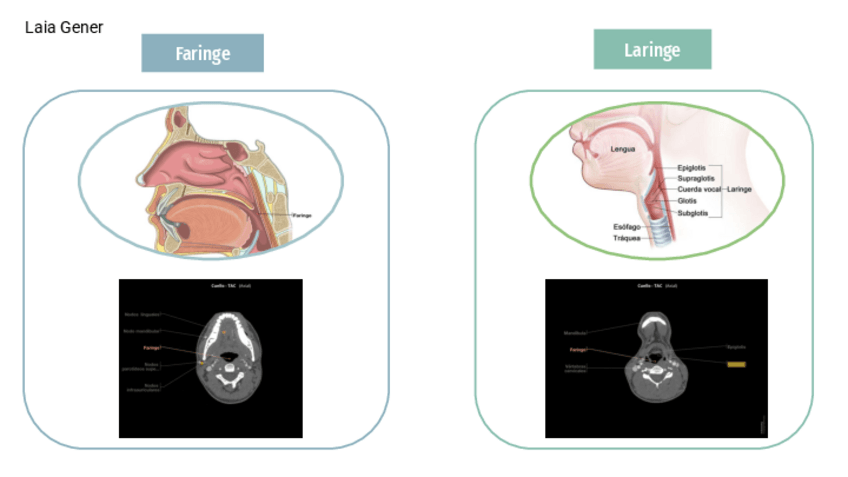

He publicado nuevos apuntes de Anatomía por la imagen: TEMA-3-cabeza.pdf

9 páginas